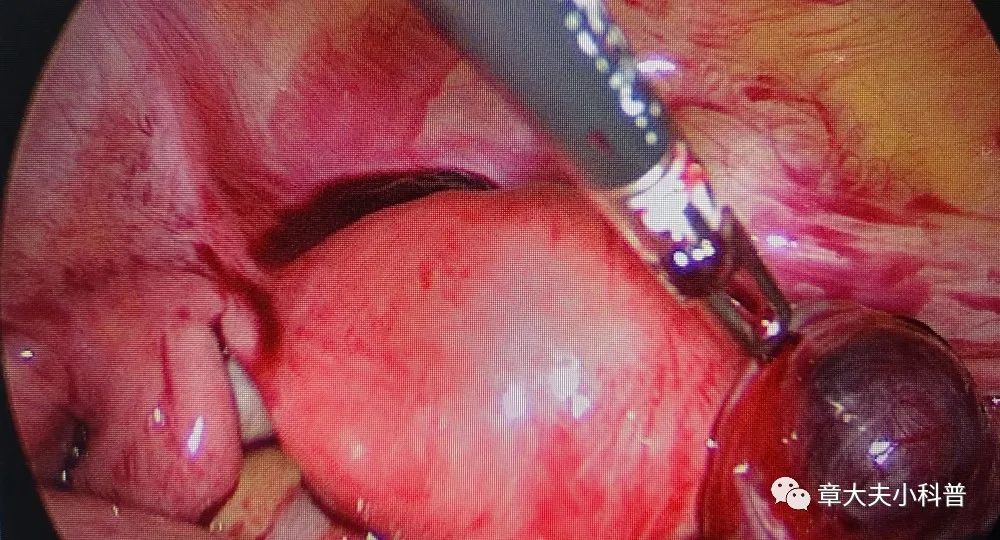

腹腔镜探查

见右侧卵巢

黄体破裂,

腹腔内出血,

1300ml